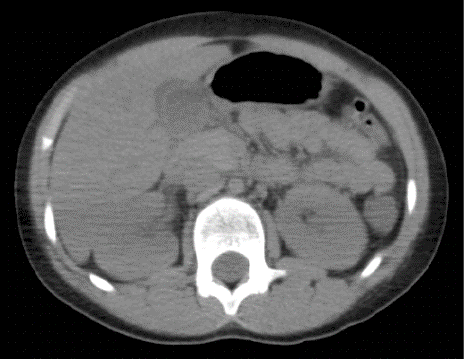

Mientras que dentro del estudio de TAC de abdomen realizado a 13 pacientes el principal hallazgo fue la presencia de líquido perivesicular en 4 (30,76%) de ellos (figura 1 y 2).

Cabe mencionar que ante la duda diagnóstica tanto del pediatra en primera línea como del cirujano pediatra, se realizó estudios de imágenes complementarios tales como ecografía o tomografía de abdomen en determinados pacientes. El principal hallazgo de estas ayudas diagnósticas fueron las alteraciones perivesiculares en el 30% de los casos. Razón por la que sugerimos que ante pacientes con sospecha clínica de apendicitis que presenten clínica o nexo epidemiológico de COVID-19 se considere realizar TAC de abdomen previo al procedimiento. Una revisión sistemática previamente ha reportado que hasta un 34% de los pacientes pediátricos no presentaron ningún hallazgo en tomografía de tórax [18], mientras que en este estudio todos los pacientes mostraron diferentes alteraciones en la imagen pulmonar como se mencionó en los resultados, lo cual podría estar relacionado a las complicaciones que desarrollaron estos pacientes ya sea desde el momento de su ingreso hospitalario o durante la estancia en el mismo.